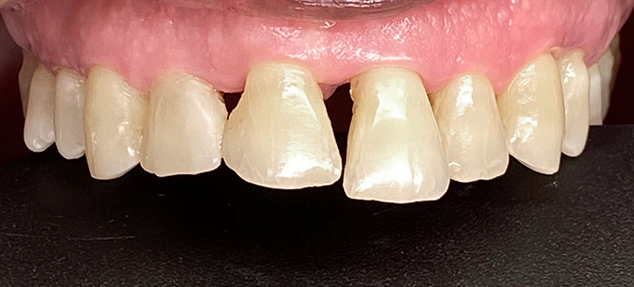

Une patiente de 70 ans s'est présentée avec une perte osseuse sévère et des triangles noirs extrêmes dus à des décennies de maladie parodontale (Fig. 1). Les principales plaintes de la patiente comprenaient des espaces inesthétiques entre ses dents et une incapacité à prononcer certains mots en raison de son choc avec l'incisive centrale supérieure gauche chaque fois que sa mâchoire avançait pour prononcer les "T" et les "D" (Fig. 2).

FIG. 1

Patiente de 70 ans atteinte de parodontite chronique mais stable,

qui consulte pour des options de fermeture de ses triangles noirs.